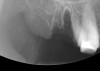

Figure 15  After extraction, the outline of the socket is  visualized radiographically.

Figure 15

Figure 16  Radiograph showing the site after it was filled with the resorbable bone graft material and covered with the PTFE barrier.

Figure 16